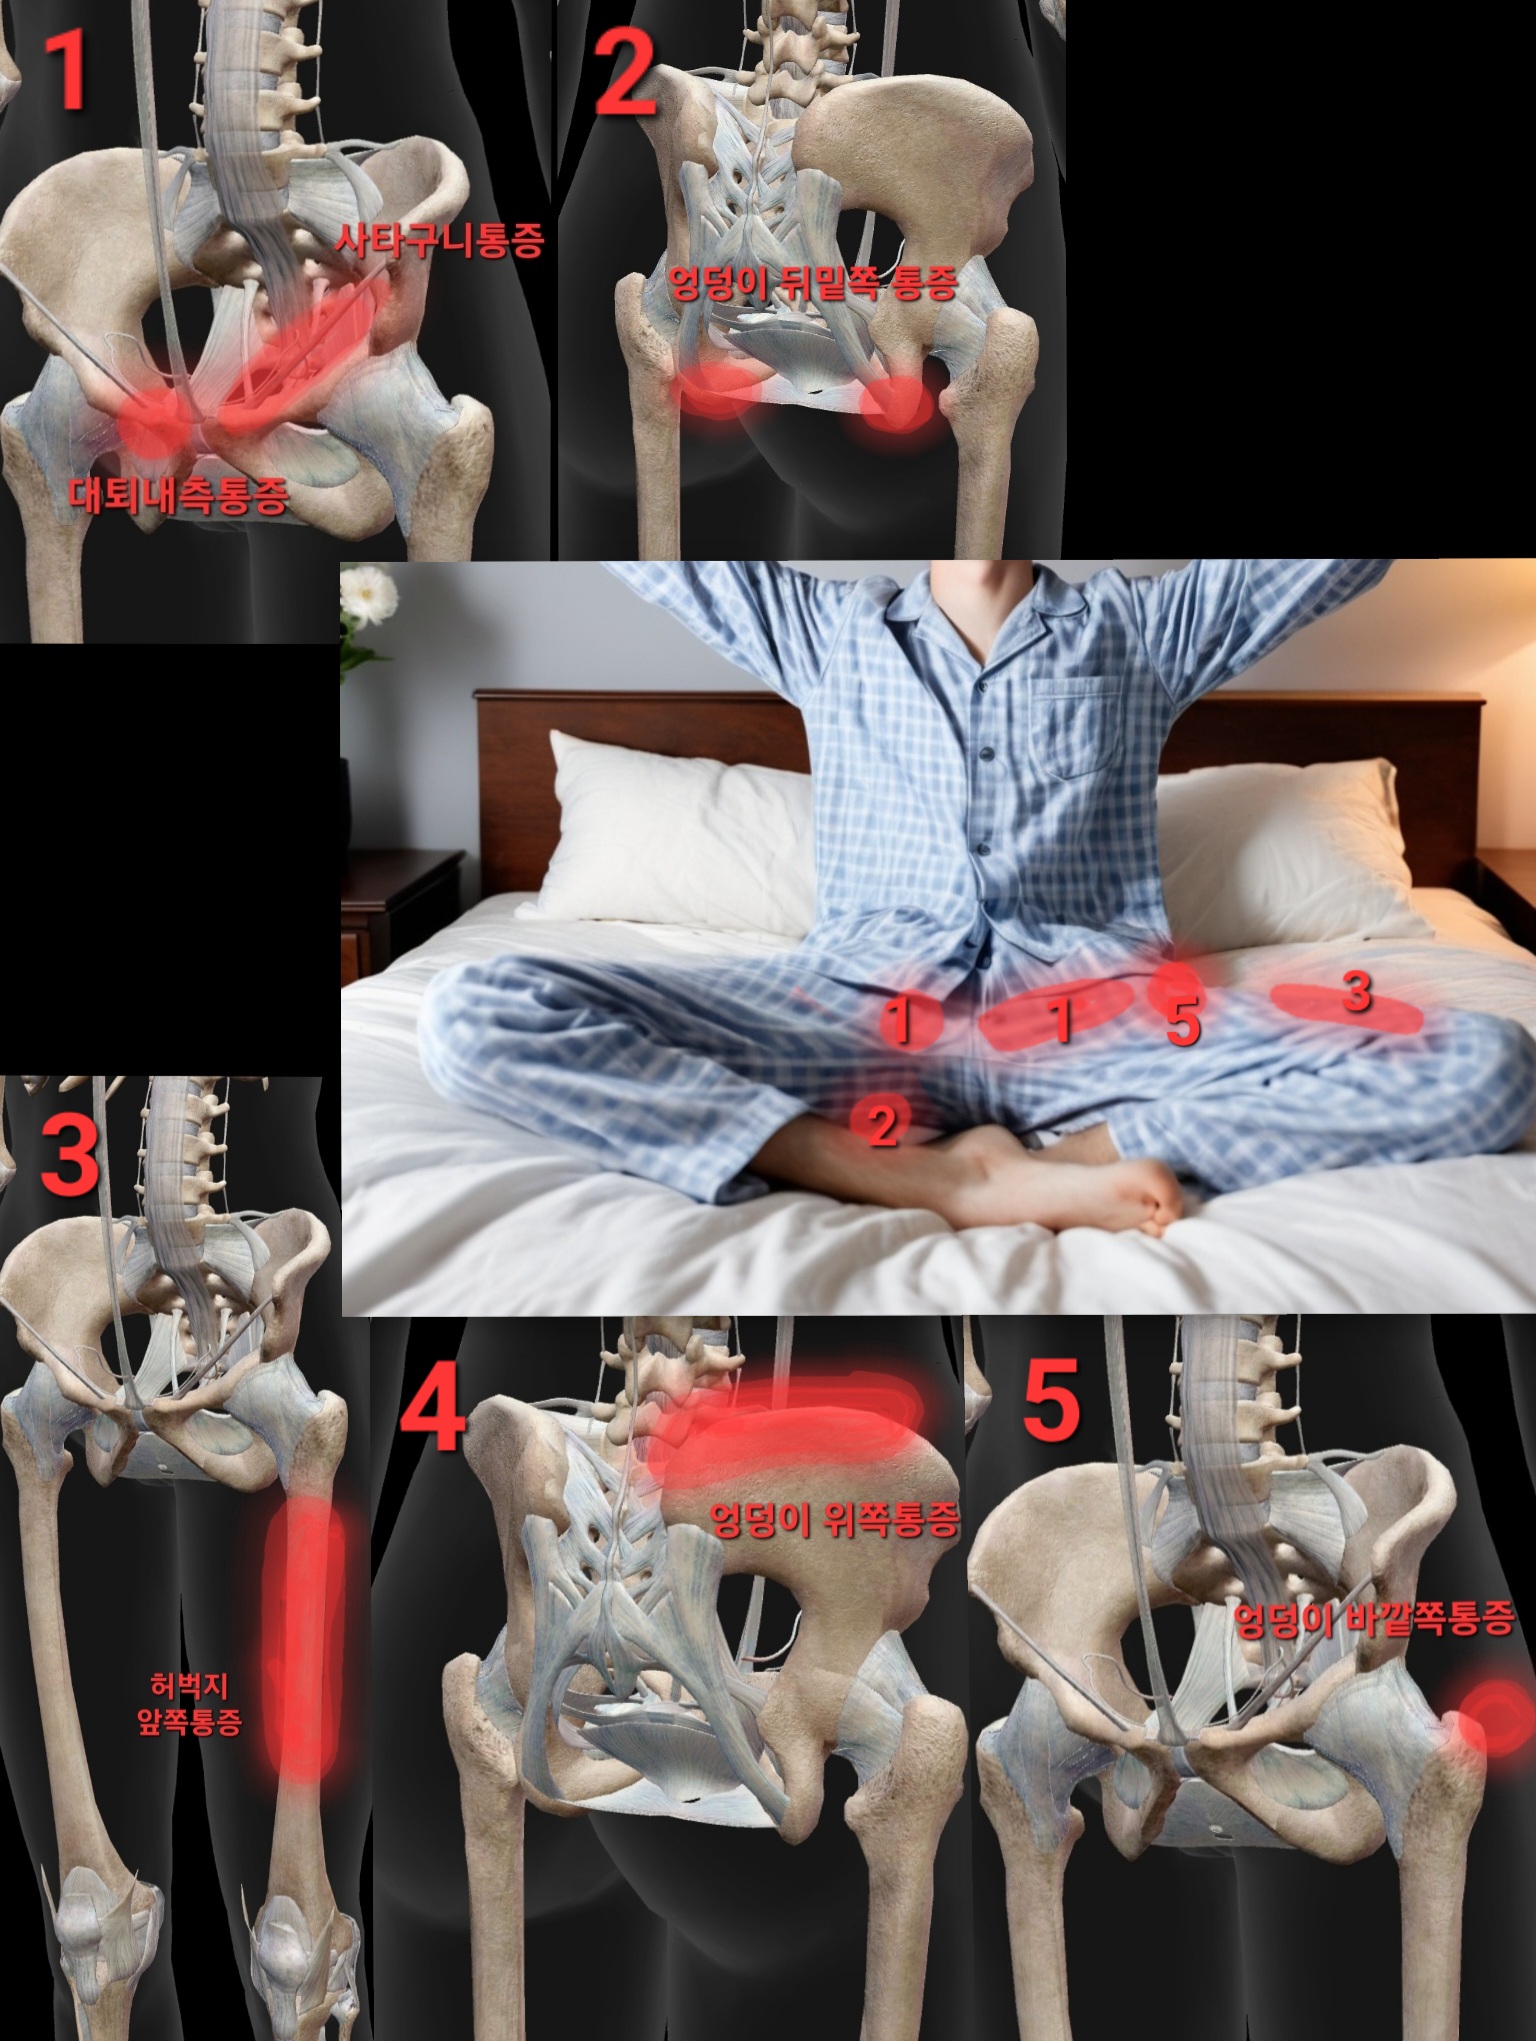

엉덩이 바깥쪽통증 (고관절 옆, 대퇴부 측면통증)

양반다리시 고관절이 안으로 말리면서 충돌(FAI)이 주로 앞쪽(사타구니)에서 발생하지만 다른 원인으로 엉덩이 바깥쪽으로 통증을 호소하기도 합니다

엉덩이 뒤밑쪽 통증 (좌골 주변 통증)

앞쪽 사타구니 통증 & 대퇴부 내측 집중통증

엉덩이 위쪽통증 (허리와 골반 연결 부위통증)

양반다리 허벅지 통증 (허벅지 앞쪽통증 대퇴사두근)